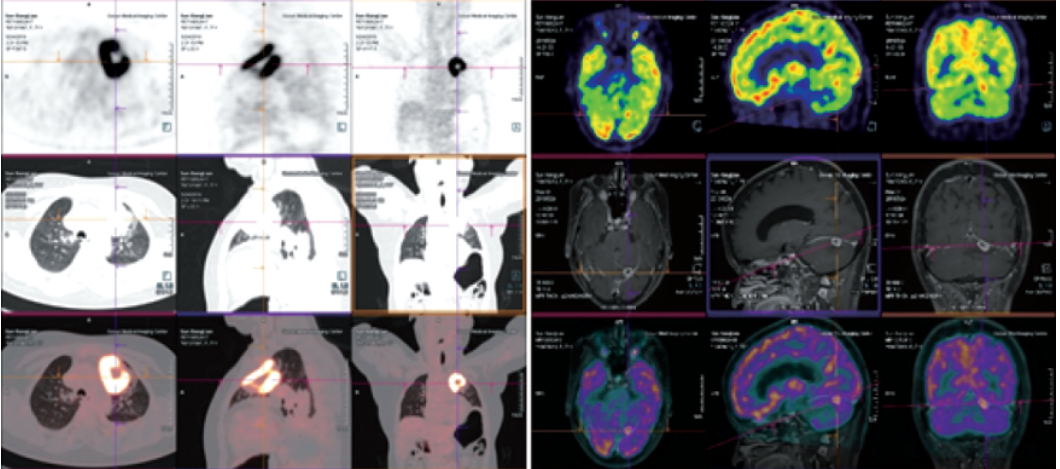

西門子新一代正電子發(fā)射及計算機斷層掃描系統(tǒng)

Biograph mCT Flow

?PET/CT在全身腫瘤的早期篩查、早期診斷及良惡性鑒別上、惡性腫瘤的分期、分級、尋找腫瘤原發(fā)病灶、評估療效及監(jiān)測腫瘤復(fù)發(fā)等具有重要價值。

?精準(zhǔn):本設(shè)備是新一代PET/CT,圖像重建矩陣可達400×400,其分辨率達到毫米級;其FlowMotion掃描技術(shù)提供極精細器官細節(jié)顯示,并對病灶提供可重復(fù)定量分析;顯著提高了微小病灶的檢出和確診率。

?全面:PET/CT是通過血管內(nèi)注射示蹤劑,采用動態(tài)連續(xù)掃描全身,動態(tài)數(shù)據(jù)分析,跟蹤檢查精準(zhǔn)定位,全身病變無處遁形。

?快速:本設(shè)備采用流式掃描技術(shù),在3-5分鐘可以完成高質(zhì)量的全身掃描,具有掃描速度快、靈敏度高的特點,可快速檢查全身,提高舒適度和診斷效率。

案例圖